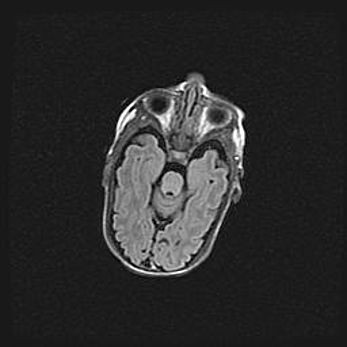

Множественные кисты обоих полушарий головного мозга, наибольшая из них в правой затылочной области. Ассиметричная атрофическая гидроцефалия.

Возраст: 7 месяцев

Вес: 5660 г

Пол: мужской

Окружность головы: 41,5 см

Срок гестации: 28-29 недель

Кисты головного мозга развиваются в результате многоочаговых некрозов вещества мозга и возникают вследствие перенесенной перинатальной инфекции, менингитов, энцефалитов, асфиксии, родовой травмы, расстройств мозгового кровообращения различного генеза. Образованию кист в веществе головного мозга плодов и новорожденных способствуют такие факторы, как высокое содержание в нем воды, недостаточная (или отсутствие) миелинизация и слабая астроглиальная реакция на повреждение.

Кисты могут сочетаться с гидроцефалией и другими поражениями головного мозга.